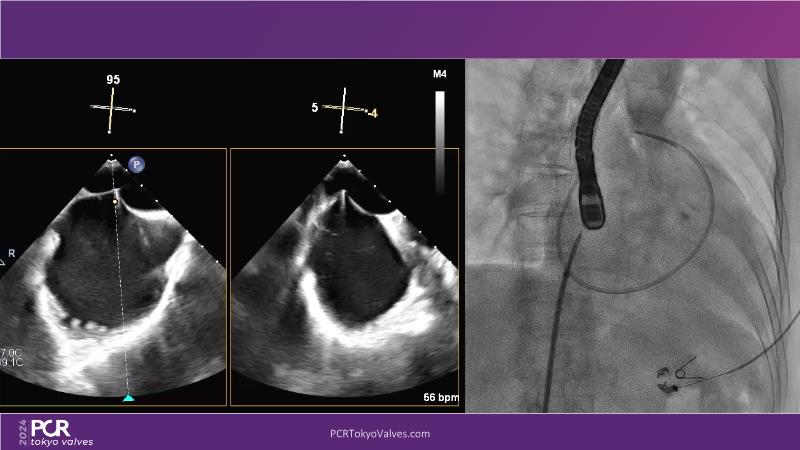

Watch this session to get an overview of a new TEER device, follow the step-by-step procedure related to initial experiences with this device for a Japanese patient with degenerative mitral regurgitation, learn about the latest data from RCT and registries, and follow discussions of challenging TEER cases!

- To learn procedural step-by-step of novel device